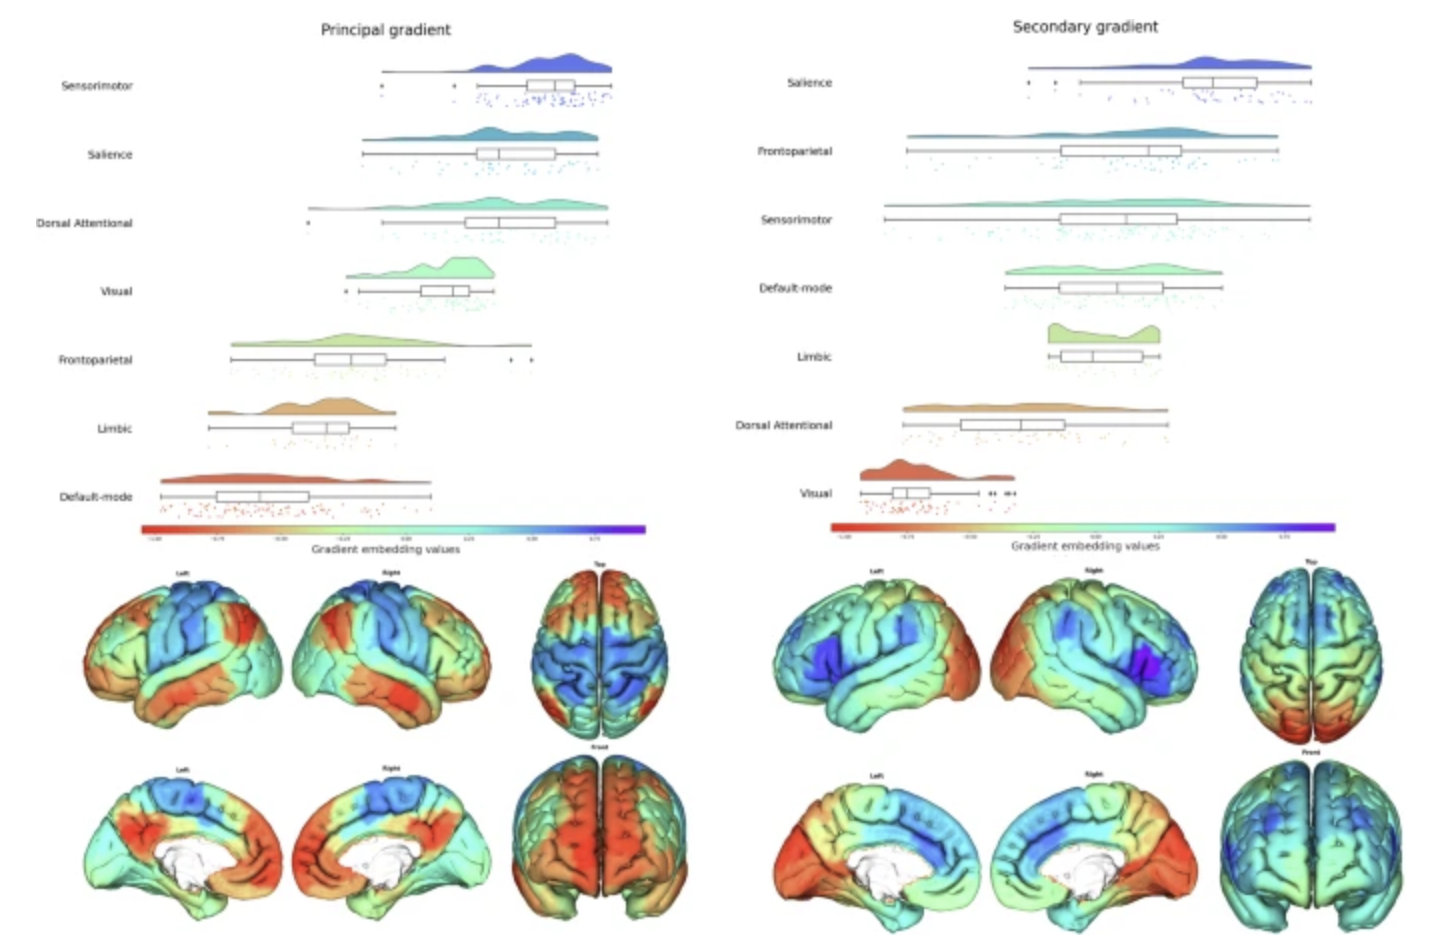

Brain Activity

Objective neural measures, including neuroimaging and brain markers, to provide insight into functional brain states.

Psychiatric assessments rely heavily on subjective clinician-rated scales (e.g., HAM-D, PANSS) or patient-reported outcomes, introducing variability and bias. Neuroimaging-based biomarkers offer objective, quantifiable endpoints that can reduce this noise and improve signal detection.

Our platform directly addresses these pain points and is designed to reduce trial failure risk by offering neuroimaging-based biomarkers that stratify patients and predict individual placebo or treatment response. Our biomarkers are grounded in robust neuroscience, clinically interpretable, and regulator-ready.

Our proprietary platform leverages machine learning to detect predictive signatures of treatment and placebo response in CNS disorders. We integrate structural and functional imaging with rigorous clinical data to deliver: